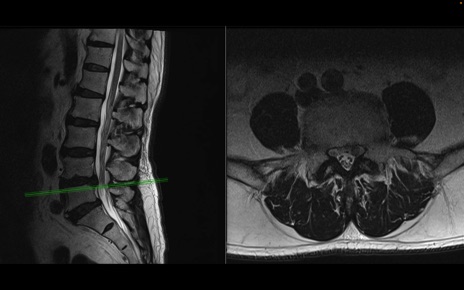

【整形】TIPS症例2 腰椎MRI 横断像と矢状断像

【症例】70歳代男性

【主訴】左下肢痛

【現病歴】2週間前くらいから腰痛、左下肢痛あり。左臀部から大腿、下腿外側のしびれが常時ある。歩行とともに同部位の痛みあり。

【身体所見】Lasegue70-/60+、Bragard-/±、PTR ±/±、ATR -/-、IP 5/5、TA 5/4、TS 5/5、EHL 右第1足趾なし/3、FHL 5/5、hypersthesia(-)、足背動脈触知良好

異常所見と診断は?